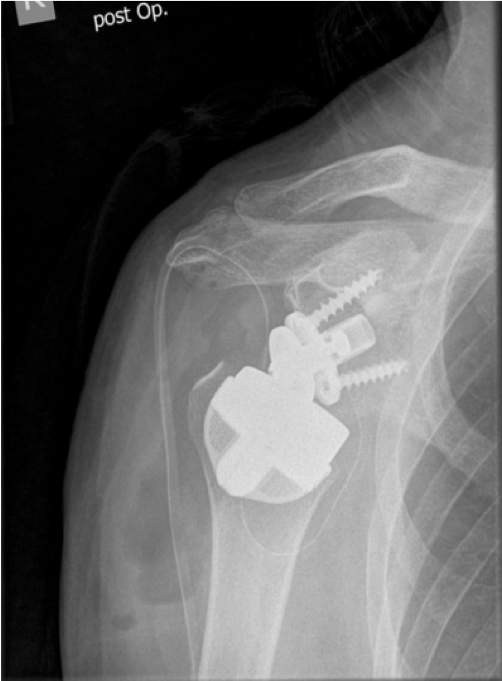

Post-op

Implantation of the LINK Embrace

- StemlessRing Cage with the TrabecuLink structure for bone integration,

- Eccentric PE-Glenosphere with 39 mm diameter and CoCr Reverse Insert with a 10° inclination